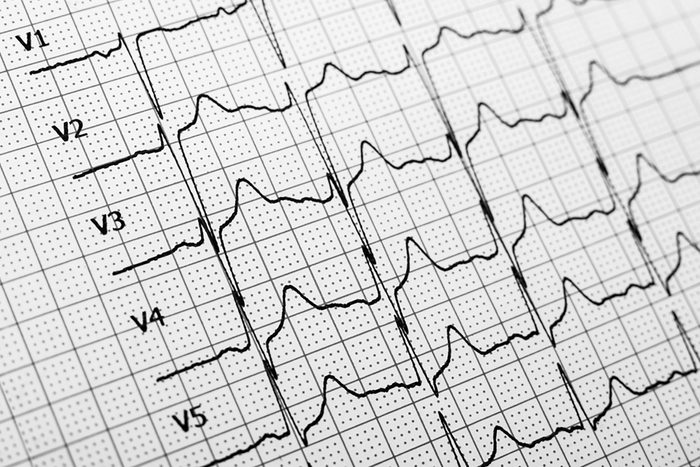

20 minutes later: Cardiovascular improvements

In as little as 20 minutes, “your heart rate returns to normal, your blood pressure drops, and your circulation starts to normalize,” says Nikola Djordjevic, MD, project manager of Med Alert Help.

One day later: Heart attack risk falls

According to a 2018 study published in the American Journal of Preventive Medicine, daily e-cigarette use doubles a person’s risk for a heart attack. If you quit, however, the risk begins to fall very quickly. “After just one day, your heart attack risk starts to decrease thanks to the lowering of blood pressure, rising blood oxygen levels, and reducing the negative influence on cholesterol levels and the formation of blood clots,” Dr. Djordjevic says.

After one year: Your risk of a heart attack is cut in half

Now that your blood vessels are returning to normal size, your heart rate is back to a safe pace, and your blood pressure is lowered, your risk for a heart attack is much lower than while you were still vaping. “After one year, cardiovascular risk reduces by 50%,” Dr. Djordjevic says.